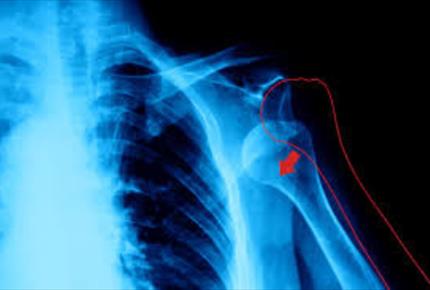

در رفتگی یا نیم دررفتگی؟-مجله مادر و کودک گوپی

در رفتگی یا نیم دررفتگی عبارت است از آسیب به مفصل به طوری که استخوانهایی که در آن مفصل در حالت طبیعی رو به روی هم قرار دارند از هم جدا شوند...